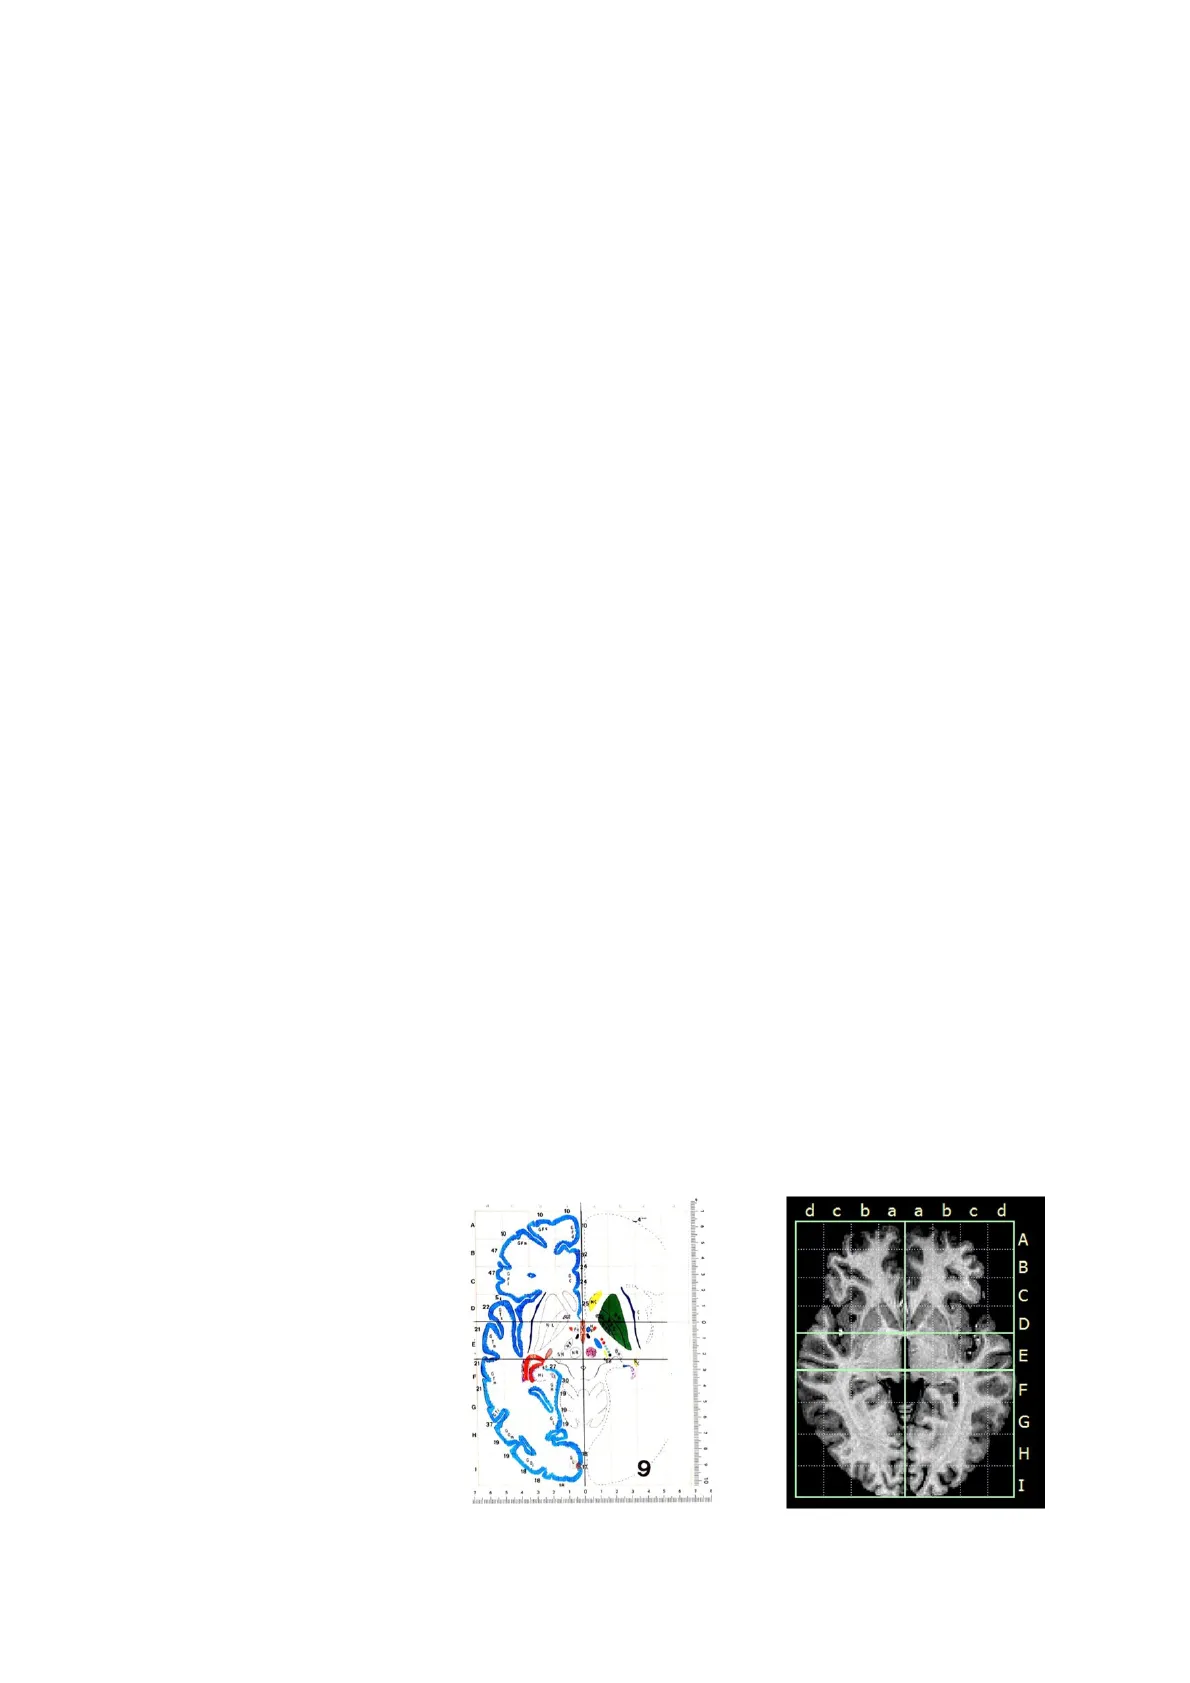

Ogni immagine dell’atlante

stereotassico è

contrassegnata in base alla

distanza della sezione

anteriormente o

posteriormente al bregma. La

griglia di ciascuna immagina

indica le distanze delle

strutture cerebrali ventrali

rispetto alla sommità del

cranio e laterali rispetto alla

linea mediana.

CHIRURGIA STEREOTASSICA La stereotassi indica la capacità di localizzare gli oggetti nello spazio. L'apparato stereotassico è costituito da un fermatesta, che fissa in posizione standard il cranio dell'animale, e un reggielettrodo, che sposta l'elettrodo e la cannula nelle tre dimensioni spaziali, secondo distanze misurate. Per eseguire un simile intervento è necessario studiare prima un atlante stereotassico: è un libro, un sito web o un software che contiene immagini che corrispondono alle sezioni frontali del cervello effettuate a varie distante mostrali e caudali rispetto al bregma. Il cranio è costituito da diverse ossa, che crescono insieme e formano suture (giunture). La testa dei neonati contiene un punto molle a livelle dell'intersezione tra la satura sagittale e quella coronale, chiamato fontanella. Quando l'intervallo tra le suture si richiude, il punto d'intersezione è denominato bregma, dal termine greco che significa "porzione frontale della testa". Ogni immagine dell'atlante stereotassico è contrassegnata in base alla distanza della sezione anteriormente o posteriormente al bregma. La griglia di ciascuna immagina indica le distanze delle strutture cerebrali ventrali rispetto alla sommità del cranio e laterali rispetto alla linea mediana. € 0 -- D E . 27 F 21 F G I - 9 dc baa b c d A B C 22 O G H IL'APPARATO STEREOTASSICO L'apparato stereotassico include un fermatesta, che mantiene il cranio dell'animale nella posizione adeguata, un reggielettrodo o reggicannula, e un meccanismo calibrato che muove il reggielettrodo/reggicannula secondo distanze misurate lungo i tre assi: anteriore-posteriore, dorsale-ventrale e laterale-mediale. Una volta trovate le coordinate su un atlante stereotassico, si anestetizza l'animale, si posiziona l'apparato e si incide lo scalpo. Dopo la localizzazione del bregma, si riportano i numeri appropriati sull'apparato stereotassico, si perfora il cranio con il trapano e si inserisce il reggielettrodo nel cervello alla corretta profondità. In questo modo, la punta dell'elettrodo o della cannula è portata esattamente nell'area desiderata e si può procedere con la lesione. Esistono anche apparati stereotassici da utilizzare sull'uomo. Talvolta i neurochirurghi producono lesioni sottocorticali: ad esempio, per ridurre i sintomi della malattia di Parkinson. O O